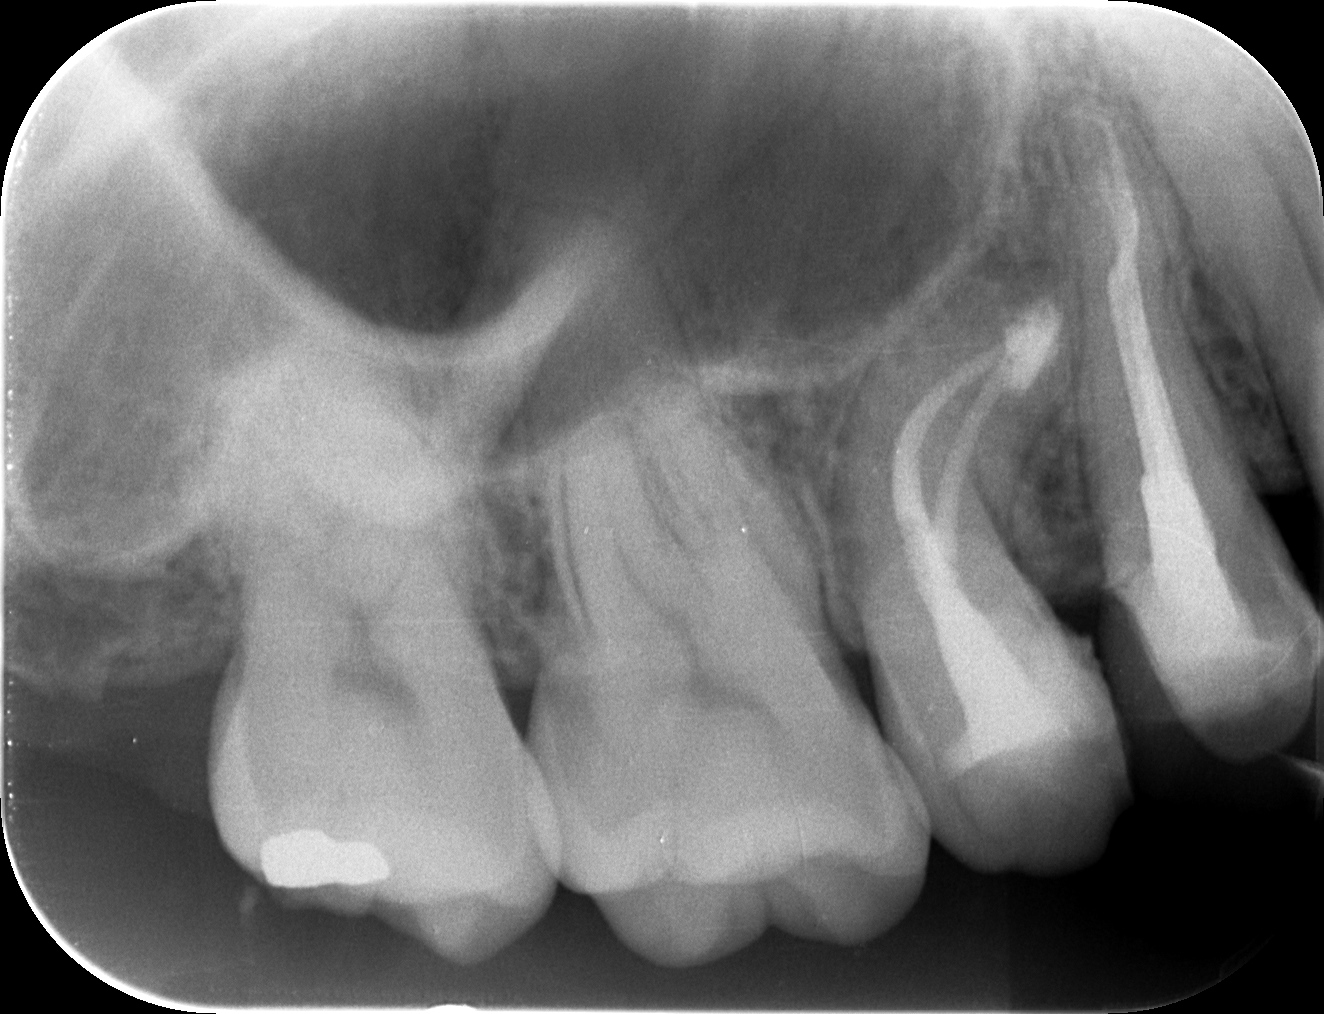

#4 Apicoectomy 1.5yr recall(2025.6.18)

術前・術後を比較した。

上部構造は1.5年間,プロビジョナルレストレーションであったが治癒した。

経過観察も終診でいいだろう。